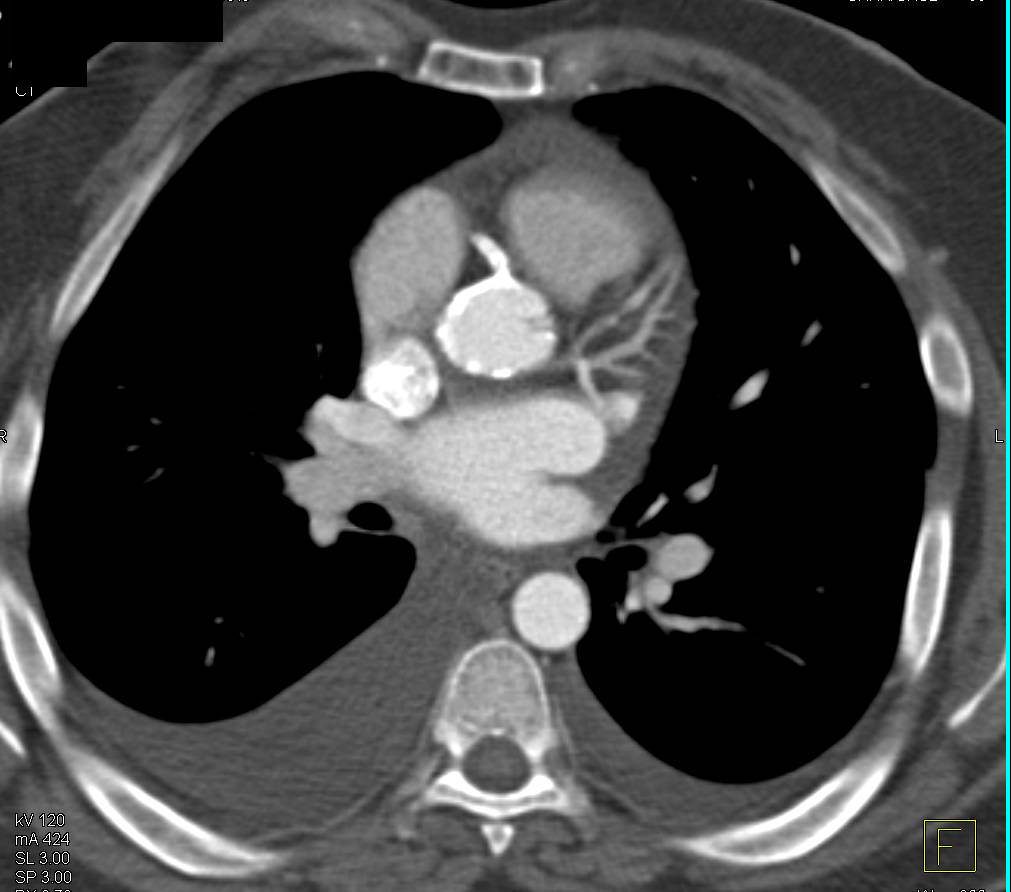

Endovascular Stent with Left Occluders